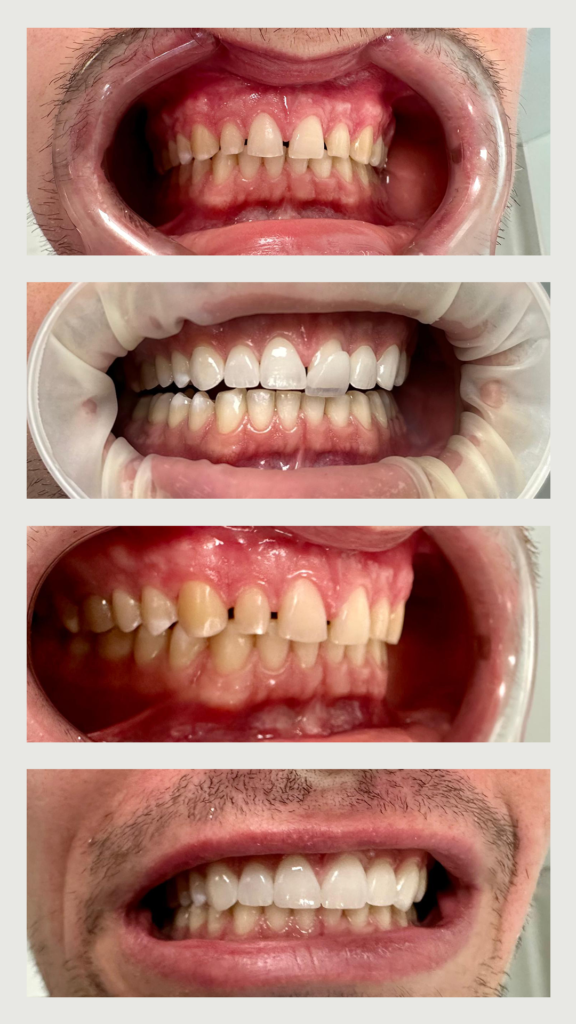

Pacientul s-a prezentat la clinica noastră fiind nemulțumit de 𝐚𝐬𝐩𝐞𝐜𝐭𝐮𝐥 𝐢𝐧𝐞𝐬𝐭𝐞𝐭𝐢𝐜 al arcadei maxilare datorat spațierilor dentare.

Astfel:

pacientul a purtat 𝐚𝐩𝐚𝐫𝐚𝐭 𝐝𝐞𝐧𝐭𝐚𝐫 pentru a închide spațiile de la arcada inferioară

am poziționat caninii în raport neutral

am decis închiderea spațiilor frontale maxilare cu ajutorul a 6 fațete 𝐞-𝐌𝐚𝐱

am realizat 𝐚𝐥𝐛𝐢𝐫𝐞 𝐝𝐞𝐧𝐭𝐚𝐫ă pentru a putea alege fațete mai deschise la culoare